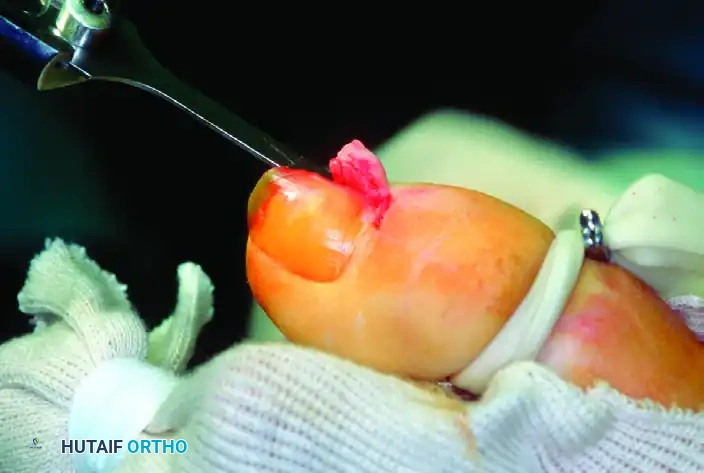

Intraoperative exposure of the glomus tumor utilizing a matrix-sparing approach.

3. Tumor Identification: Reflect the skin and matrix flap dorsally and inspect the deep (volar) surface of the flap. The glomus tumor is usually obvious within the sub-matrix tissue, appearing as a ball-shaped or egg-shaped, opaque, semi-elastic, bluish-red structure.